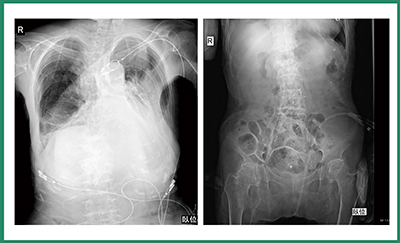

例えば,胸部撮影においては肺野内の血管影が末梢まで明瞭に描出されており,縦隔や横隔膜,心臓の周囲も明瞭に観察することができる。頸椎撮影では下顎や後頭部近傍や側面撮影においても肩との重なり部分の描出が非常に向上した。また,CRで整形外科領域の撮影を行う際には,骨梁がはっきりと見えるよう強調表示をかけて出力していたが,CALNEO Smartではそれよりもかなり画質が向上している(図1)。

図1 整形外科領域におけるCRとCALNEO Smartの画像比較